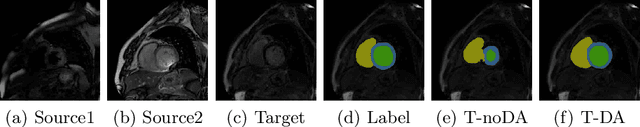

Abstract:Accurate computing, analysis and modeling of the ventricles and myocardium from medical images are important, especially in the diagnosis and treatment management for patients suffering from myocardial infarction (MI). Late gadolinium enhancement (LGE) cardiac magnetic resonance (CMR) provides an important protocol to visualize MI. However, automated segmentation of LGE CMR is still challenging, due to the indistinguishable boundaries, heterogeneous intensity distribution and complex enhancement patterns of pathological myocardium from LGE CMR. Furthermore, compared with the other sequences LGE CMR images with gold standard labels are particularly limited, which represents another obstacle for developing novel algorithms for automatic segmentation of LGE CMR. This paper presents the selective results from the Multi-Sequence Cardiac MR (MS-CMR) Segmentation challenge, in conjunction with MICCAI 2019. The challenge offered a data set of paired MS-CMR images, including auxiliary CMR sequences as well as LGE CMR, from 45 patients who underwent cardiomyopathy. It was aimed to develop new algorithms, as well as benchmark existing ones for LGE CMR segmentation and compare them objectively. In addition, the paired MS-CMR images could enable algorithms to combine the complementary information from the other sequences for the segmentation of LGE CMR. Nine representative works were selected for evaluation and comparisons, among which three methods are unsupervised methods and the other six are supervised. The results showed that the average performance of the nine methods was comparable to the inter-observer variations. The success of these methods was mainly attributed to the inclusion of the auxiliary sequences from the MS-CMR images, which provide important label information for the training of deep neural networks.

Abstract:Automatic and accurate segmentation of the ventricles and myocardium from multi-sequence cardiac MRI (CMR) is crucial for the diagnosis and treatment management for patients suffering from myocardial infarction (MI). However, due to the existence of domain shift among different modalities of datasets, the performance of deep neural networks drops significantly when the training and testing datasets are distinct. In this paper, we propose an unsupervised domain alignment method to explicitly alleviate the domain shifts among different modalities of CMR sequences, \emph{e.g.,} bSSFP, LGE, and T2-weighted. Our segmentation network is attention U-Net with pyramid pooling module, where multi-level feature space and output space adversarial learning are proposed to transfer discriminative domain knowledge across different datasets. Moreover, we further introduce a group-wise feature recalibration module to enforce the fine-grained semantic-level feature alignment that matching features from different networks but with the same class label. We evaluate our method on the multi-sequence cardiac MR Segmentation Challenge 2019 datasets, which contain three different modalities of MRI sequences. Extensive experimental results show that the proposed methods can obtain significant segmentation improvements compared with the baseline models.